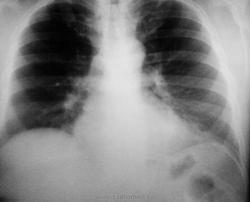

Мужчина 1973 г.р. Гиперстеник. Жалоб не предъявляет. Можно ли расценить затемнение в переднем кардиодиафрагмальном углу слева как абдоминомедиастинальную липому или есть ещё какие-нибудь варианты?( всегда это левый передний кардиодиафрагмальный угол вызывает затруднения!)

Вот снимкм.